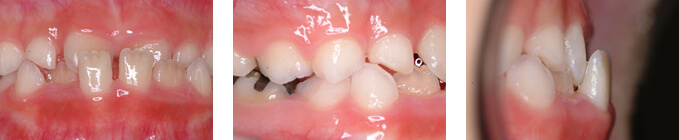

下顎後退による上顎前突

| 年齢 | 11歳女性 |

|---|---|

| 治療期間と通院回数 | 1年6か月/18回 |

| 治療費総額 | 29.4万円 |

| 主訴 | 出っ歯 |

| 診断名 | 骨格性上顎前突 |

| 主な治療装置 | バイオネーター |

| 抜歯部位 | 非抜歯 |

| リスクについて | バイオネーターは骨格タイプによって効果が大きい装置です。また、骨格的に向いている症例でも目標の成長量を達成できないことがあります。 |

治療前

治療後

この症例の解説

下顎が小さいことによって上の歯列が出て見える症例です。

下顎の成長を促すためにバイオネイターという装置を、就寝時を含めて1日12時間装着してもらいました。

約1年半で、いわゆる「出っ歯」が改善しました。